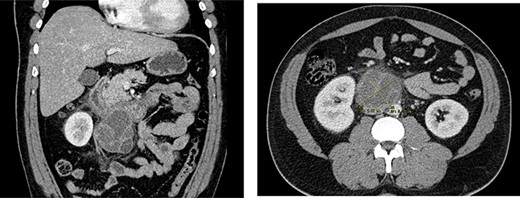

Laboratory analysis revealed leucocytosis with neutrophilia and elevated C-reactive protein. Chest X-ray was normal. In the abdominal ultrasound, a 75 × 50-mm mass in topography adjacent to the duodenum was diagnosed. Abdominal CT scan displayed a complex retroperitoneal mass, predominantly cystic, adjacent to the duodenal third portion, with local inflammatory signs, without adenomegalies or other abnormalities (Fig. 1).